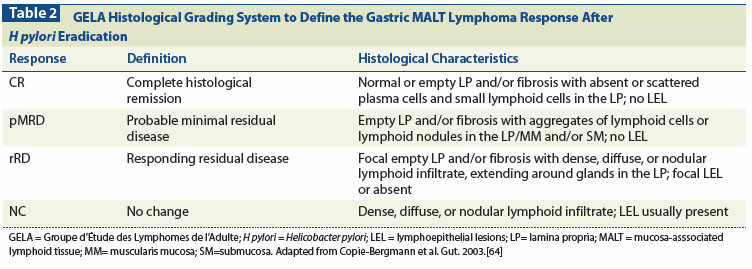

Tx: 50% will not improve c treatment of underlying H pylori

- posttreatment histo grading system based on eval of lymphoid infiltrate, LEL presence, and stromal changes

can grade as "Complete Histological Response (CR)", "Probable minimal residual dz (pMRD)", "Responding Residual Dz (r-RD)" and "No Change (NC)"

- rRD implies lymphoma is present, but also has features to suggest that it is responding, which means to stay on current tx

Px: can induce long-term remission in 4/5 cases